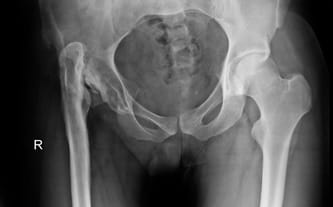

Fundraiser goal: Two-staged surgery including hip-joint reconstruction and leg lengthening

Condition after Staphylococcus aureus infection and hip-joint / femur purulent inflammation.